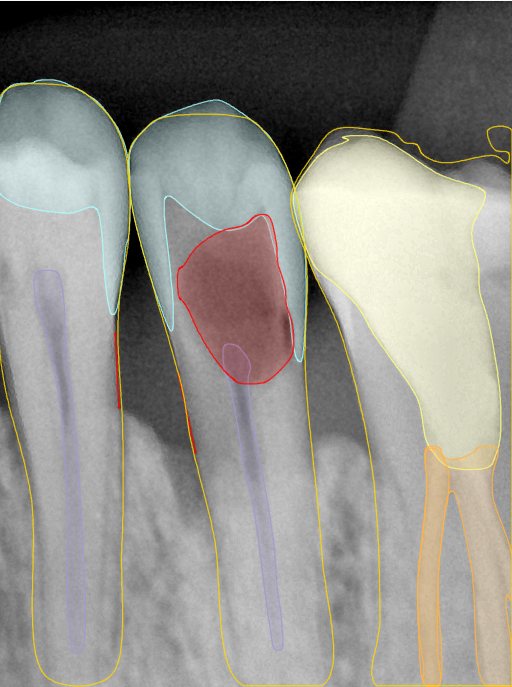

第二版算法问题测试

| 第一版 | 第二版 | 是否解决 | |

|---|---|---|---|

![]() | ![]() ![]() 边角识别有问题 龋齿识别不全 牙髓识别不全 | ![]() | 解决 |

![]() | ![]() 边角识别有问题 识别信息有误 自查(牙冠识别不全) | ![]() | 解决 |

![]() | ![]() ![]() 边角识别有误 大范围填充识别遗漏 | ![]() | 解决 |

![]() | ![]() 识别信息不全 | ![]() | 解决 |

![]() | ![]() ![]() 边角问题 牙胶识别不全 牙冠识别不全 | ![]() | 解决 |

![]() 换图片 | ![]() | ![]() 牙冠部分稍微白了一些就识别成小范围修补,部分判断异常 | 部分解决,修复类略敏感,牙冠部分稍微白了一些就识别成小范围修补,部分判断异常。 |

![]() | ![]() ![]() 牙冠识别不全 牙髓不全 根尖炎龋齿识别有误 | ![]() | 解决 |

![]() | ![]() | ![]() | 解决 |

![]() 换图片 | ![]() | ![]() | 解决 |

![]() | ![]() 牙冠识别有误 | ![]() | 解决 |

![]() 换图片 | ![]() ![]() 边角识别有误 | ![]() 修复类敏感 | 部分解决,图像过白,导致修复类判断异常。 |

![]() 换图片 | ![]() 牙冠识别不全 | ![]() 修复类敏感 | 部分解决,图像过白,导致修复类判断异常 |

结论:修复类出现了不鲁棒的情况,后续需要加入轮廓的扩充数据进行增强。